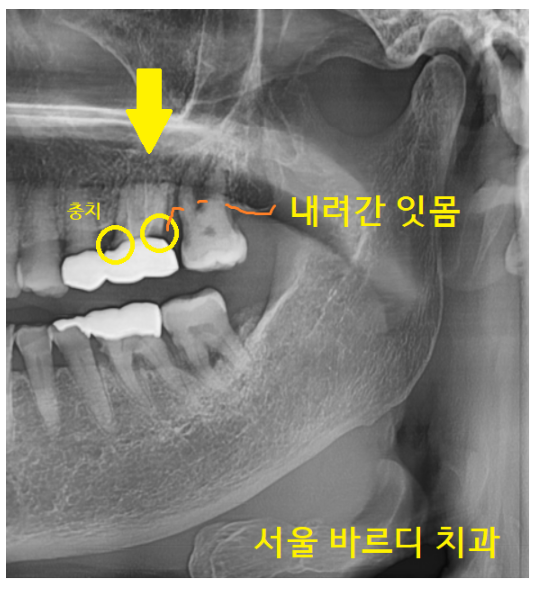

두 가지 문제가 있었습니다.

첫번째, 잇몸도 많이 내려가

맨 끝 치아는 흔들려 강일역 임플란트가 필요

두번째, 보철을 씌운 치아는 충치가 생긴 게 확인이 됩니다.

벗기고 치료를 해야 함을 설명드렸으나

환자분께서 연세가 있다 보니 그대로 쓰고 싶다 하셨습니다.

불편한 것도 크게 못느끼신다 하셨어요.

문제가 언제라도 나타날 수 있음을 말씀드리고

불편 시 방문하시라고 치료를 마무리지었습니다.